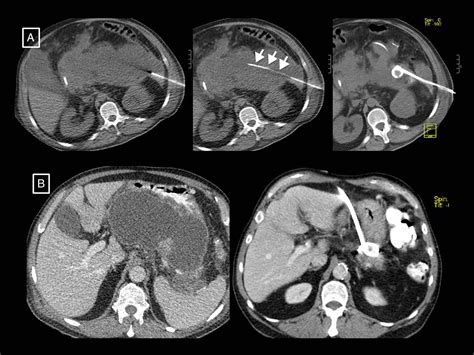

Diagnosing necrotizing pancreatitis typically requires advanced imaging. Contrast-enhanced Computed Tomography (CECT) is the gold standard for identifying areas of the pancreas that do not "enhance" or light up with dye—a hallmark sign of dead, non-perfused tissue. Magnetic Resonance Imaging (MRI) is also utilized for patients who cannot tolerate the contrast dye used in CT scans or for those with impaired kidney function.